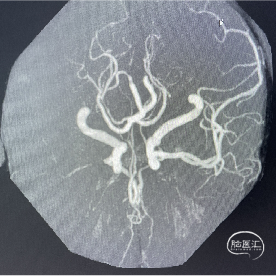

辅助检查:DWI:右侧大脑半球脑梗死灶;MRA检查:右侧大脑中动脉闭塞。

术前DSA影像:造影显示患者右侧大脑中动脉闭塞。

右侧颈内动脉造影—M1段闭塞